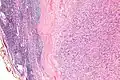

Micrograph of an intranodal palisaded myofibroblastoma. H&E stain.

IPMs are diagnosed by examination of the tissue by a pathologist. They have a rim of peripheral lymphoid tissue (remnant of a lymph node) and consist of spindle cells with nuclear palisading. Red blood cell extravasation is common and blood vessels surrounded by collagen with (fine) peripheral spokes (amianthoid fibers) are usually seen.[2]

Immunostains for smooth muscle actin and cyclin D1 are characteristically positive. The main histologic differential diagnosis is schwannoma.